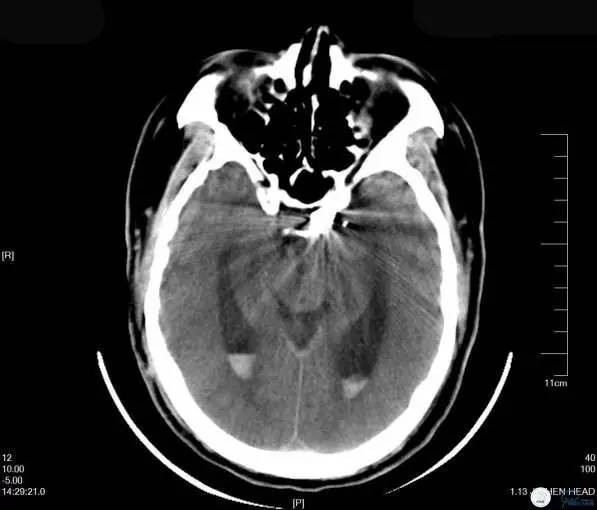

Case4 左ICA床突旁动脉瘤栓塞术后出血